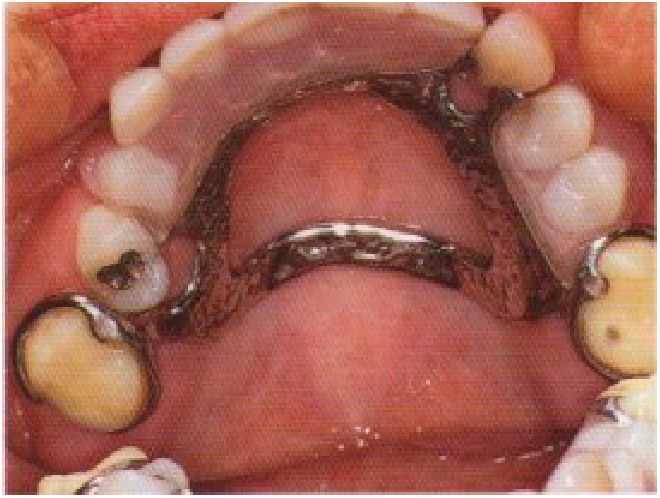

Рис. 10-13. Временные коронки, фиксированные на правом и левом первых молярах верхней челюсти, предназначенные для улучшения фиксации имеющегося частичного съемного протеза на время создания постоянных искусственных коронок и замены частичного съемного проте за.

Кроме того, при потере зубов зачастую возникает необходимость в дополнительном этапе регистрации взаимоотношений челюстей. Процедура проводится с помощью восковых базисов с окклюзионными валиками, позволяющем фиксировать рабочие модели в артикуляторе перед созданием искусственных коронок. Продолжение использования старых частичных съемных протезов в период создания искусственных коронок предъявляет особые требования к покрытию препарированных зубов временными коронками. Они необходимы для того, чтобы пациент мог пользоваться имеющимися протезами и обеспечивалась надежная фиксация во время пользования съемным протезом и при его выведении из полости рта (рис. 10-13).